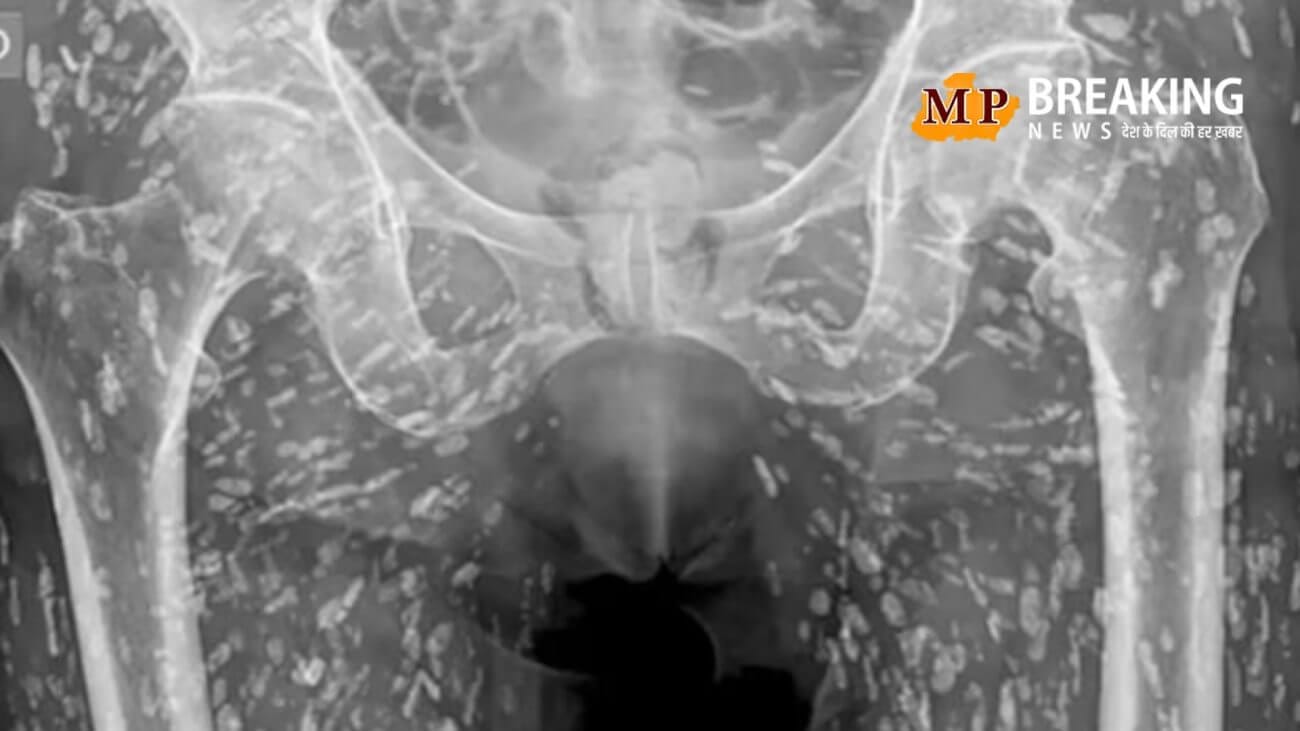

एक मरीज के एक्स-रे को देखकर डॉक्टर के होश उड़ गए। दरअसल, मरीज के शरीर के अंदर टेपवर्म का लार्वा दिखाई दिया। डॉक्टर का कहना है कि यह सिस्टिसर्कोसिस बीमारी है, जो सूअर का मांस खाने या फिर गंदगी के कारण होती है। वहीं, इस मरीज का एक्स-रे सोशल मीडिया पर तेजी से वायरल हो रहा है। इस बीमारी के बारे में डॉक्टर सैम घाली ने बताया कि इसे सिस्टिसर्कोसिस कहा जाता है।

दरअसल, एक्स-रे में अजीब सी छवि देखने को मिली है। इस सिर में ओलावृष्टि जैसी अनगिनत आयातकार छवियां देखने को मिली हैं, जिसे देखकर डॉक्टर भी हैरान रह गए। डॉक्टर का कहना है कि यह बीमारी टेपवर्म टेनिया सोलियम के लार्वा सिस्ट की मौजूदगी से होती है।

दरअसल, डॉक्टर घाली ने बताया कि यह बीमारी परजीवी लार्वा सिस्ट से संक्रमित कच्चे या अधपके सूअर के मांस को खाने से मनुष्य में होती है। इसका असर मानव की आंख, हाथ आदि पर धीरे-धीरे देखने को मिलता है। डॉक्टर घाली के मुताबिक सिस्टिसर्कोसिस लार्वा हमारे शरीर के नरम ऊतकों में प्रवेश कर जाता है और वहां सिस्ट बनाना शुरू कर देता है। इस बीमारी का जीवन चक्र कच्चे या अधपके सूअर का मांस खाने से शुरू होता है, और यह व्यक्ति में धीरे-धीरे पाचन तंत्र के माध्यम से संक्रमण फैलाना शुरू कर देता है।